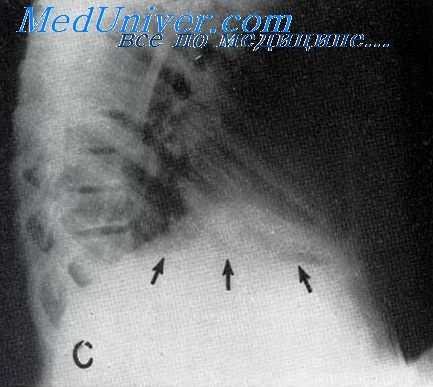

Главное значение в диагностике поддиафрагмального абсцесса отводится рентгенографии и рентгеноскопии грудной клетки. Для поддиафрагмального абсцесса характерно изменение в области ножек диафрагмы, более высокое стояние купола диафрагмы на пораженной стороне и ограничение ее подвижности (от минимальной пассивной подвижности до полной неподвижности). Скопление гноя при безгазовых поддиафрагмальных абсцессах видно как затемнение над линией диафрагмы, наличие газа – как полоса просветления с нижним горизонтальным уровнем между абсцессом и диафрагмой. Определяется выпот в плевральной полости (реактивный плеврит), снижение воздушности нижних частей легкого.

Особенно эксквизитна рентгеновская картина при газовом абсцессе; между светлым легочным полем и более светлым полем от газа узкой полоской пробегает растянутая диафрагма, совершающая дыхательные движения. Под светлым газом виден горизонтальный уровень гноя, изменяющий свое положение при наклонении больного. Картина настолько демонстративна, что сомнений относительно локализации не остается. Однако, при простом нарыве, хотя локализация и устанавливается, но может еще итти вопрос о том, нет ли внутрипеченочного заболевания, как, например, изолированного нарыва печени или поддиафрагмального эхинококка. В этих случаях даже рентгеновское исследование не позволяет поставить точного диагноза; он окончательно устанавливается только во время операции.